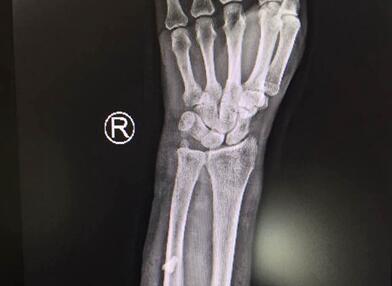

仁慈医院手足显微外科医生表示,伤者被送来时,整个右臂血肉模糊。经检查,伤者右手臂血管神经肌腱都受到了不同程度的损伤,创面大且深,而且有异物残留,经家人确认,异物是猪牙。医生立即为伤者安排了手术。

术中,在医疗器械帮助下,医生对患者进行了异物取出术,成功取出一颗长约1.5厘米的牙齿,后又进行了血管神经肌腱的修复工作,因为考虑到吴女士伤口是动物咬伤造成的,细菌较多,手术中暂不进行缝合,需要等进一步治疗完成后再行缝合。经过两个多小时的手术,吴女士手术成功。从治疗情况看,吴女士的手臂功能应该不会受到太大影响,但接下来还要进行长时间的康复训练。